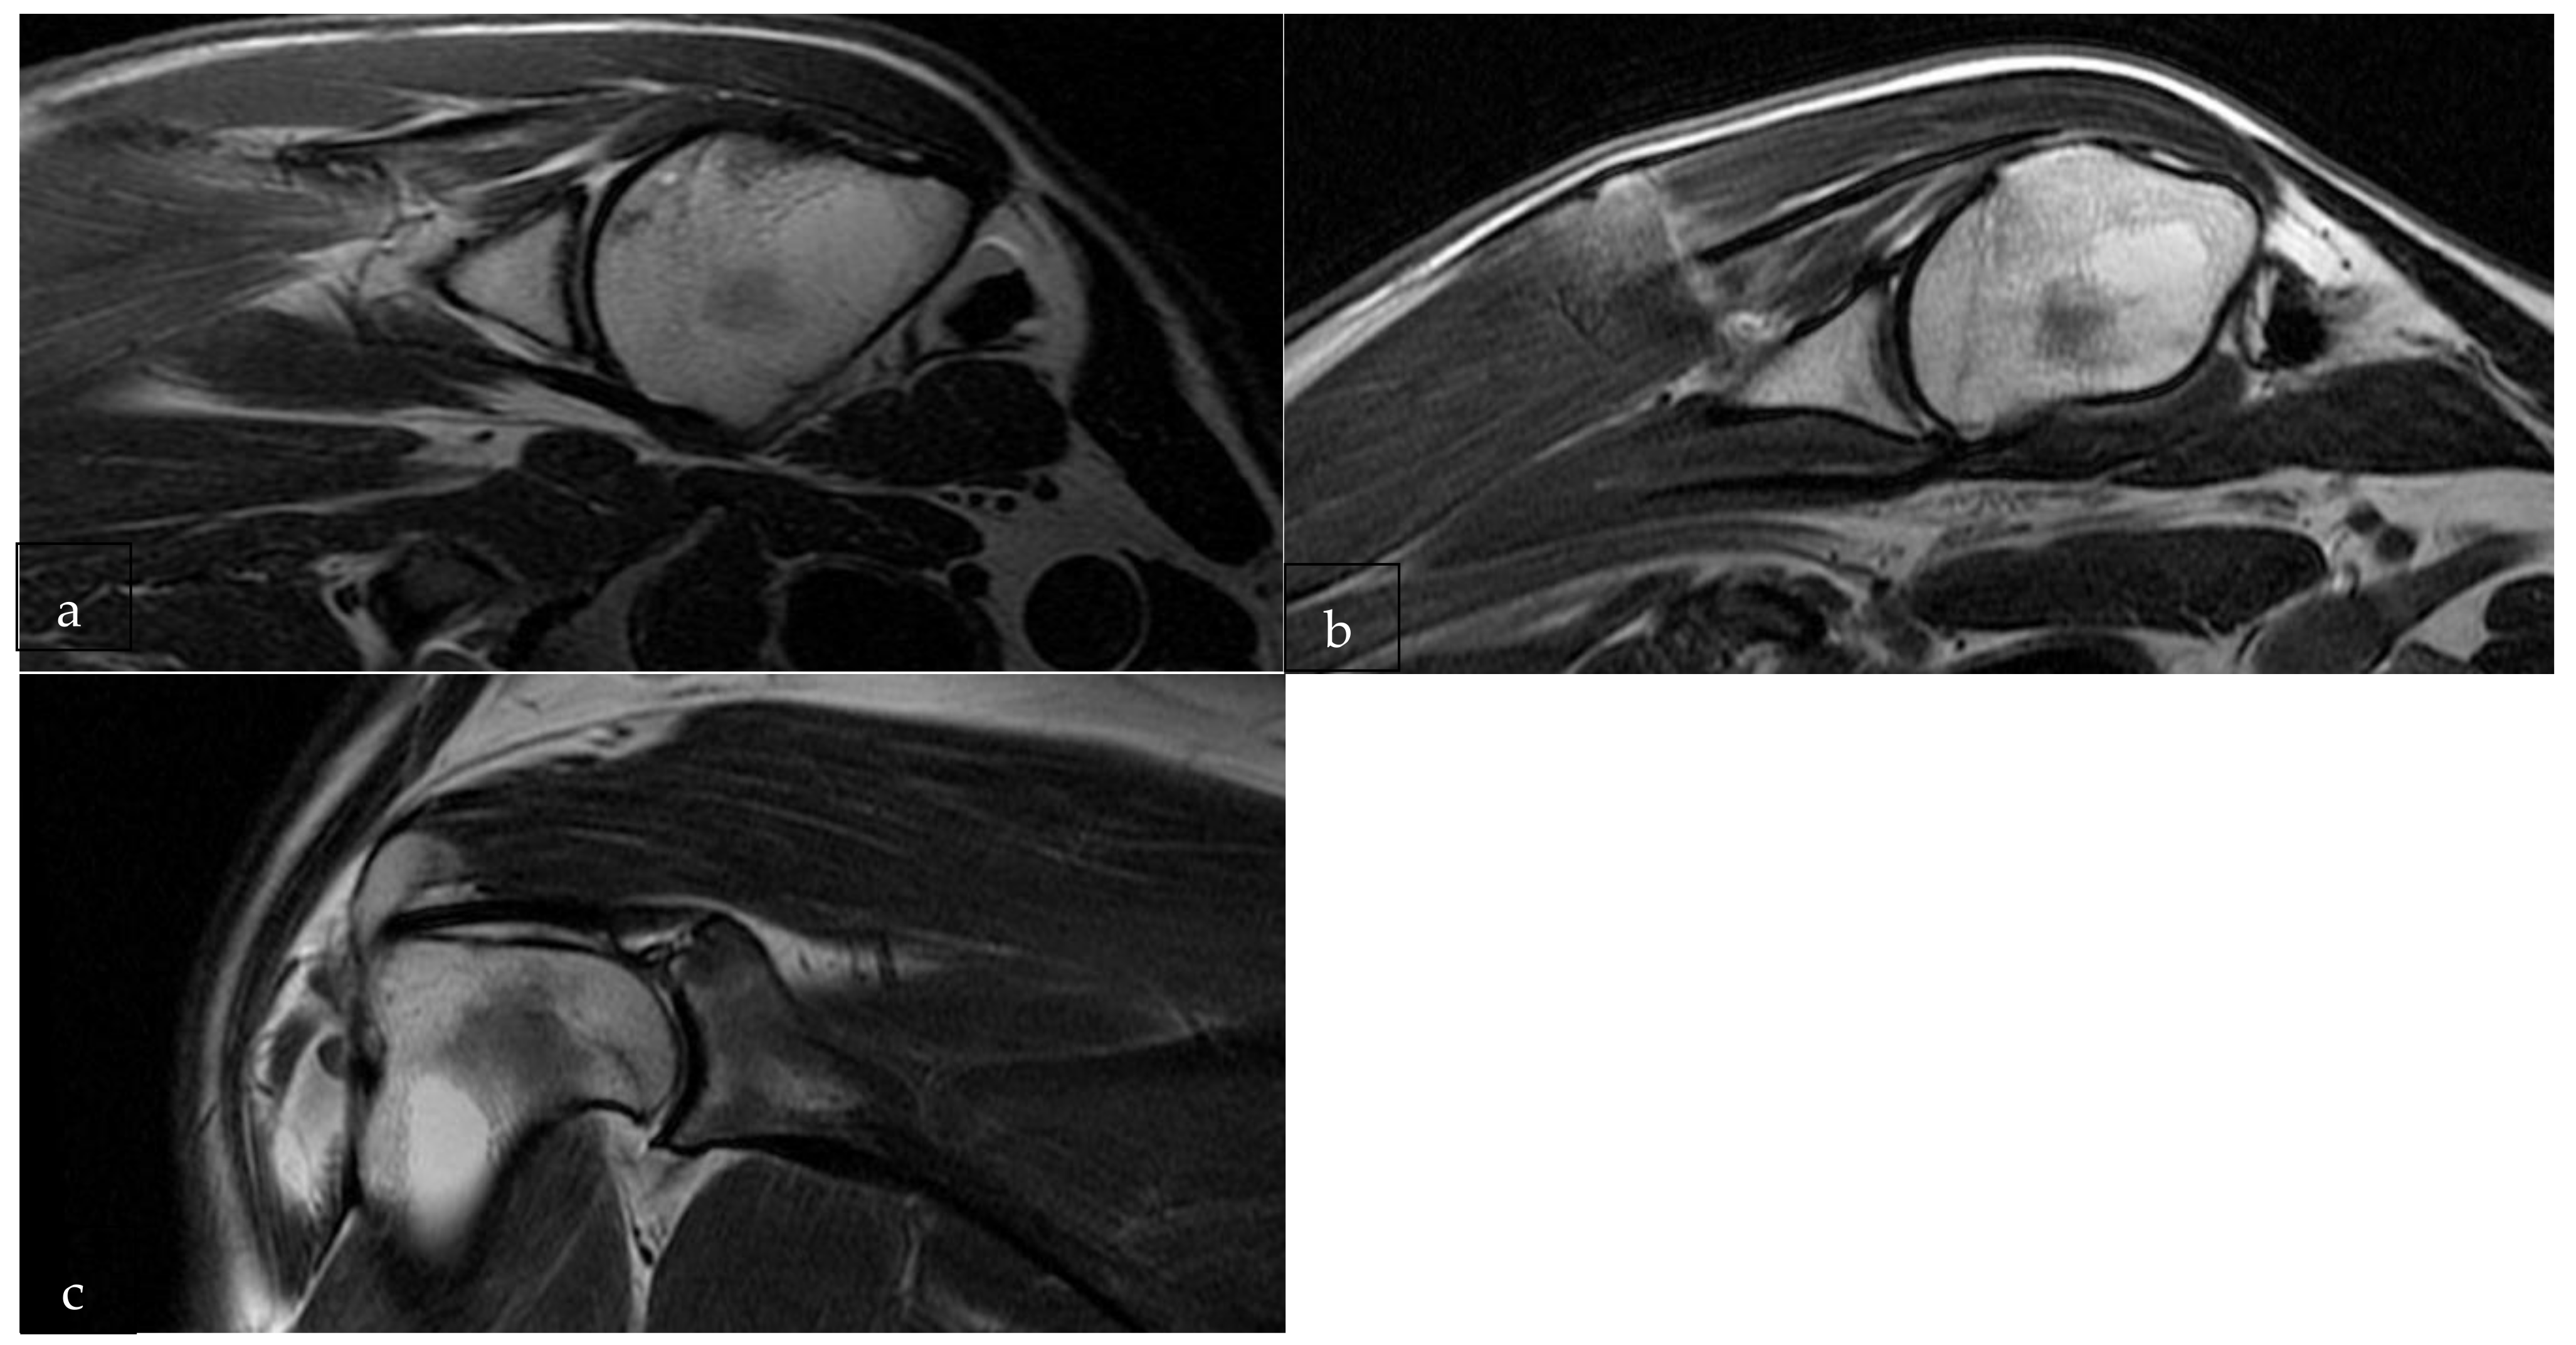

2.3. Imaging

3.1. Pre-Operative MRI Evaluation

3.2. Post-Operative MRI Evaluation